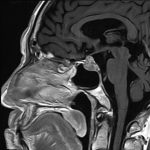

断層撮影

手術前1